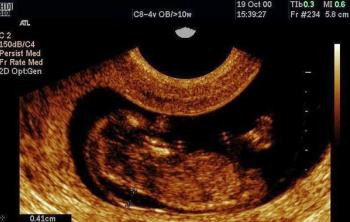

Trisomy 18 is a serious chromosomal anomaly which has a very poor (usually lethal) prognosis. T18 is usually associated with a variety of sonographically detectable abnormalities.